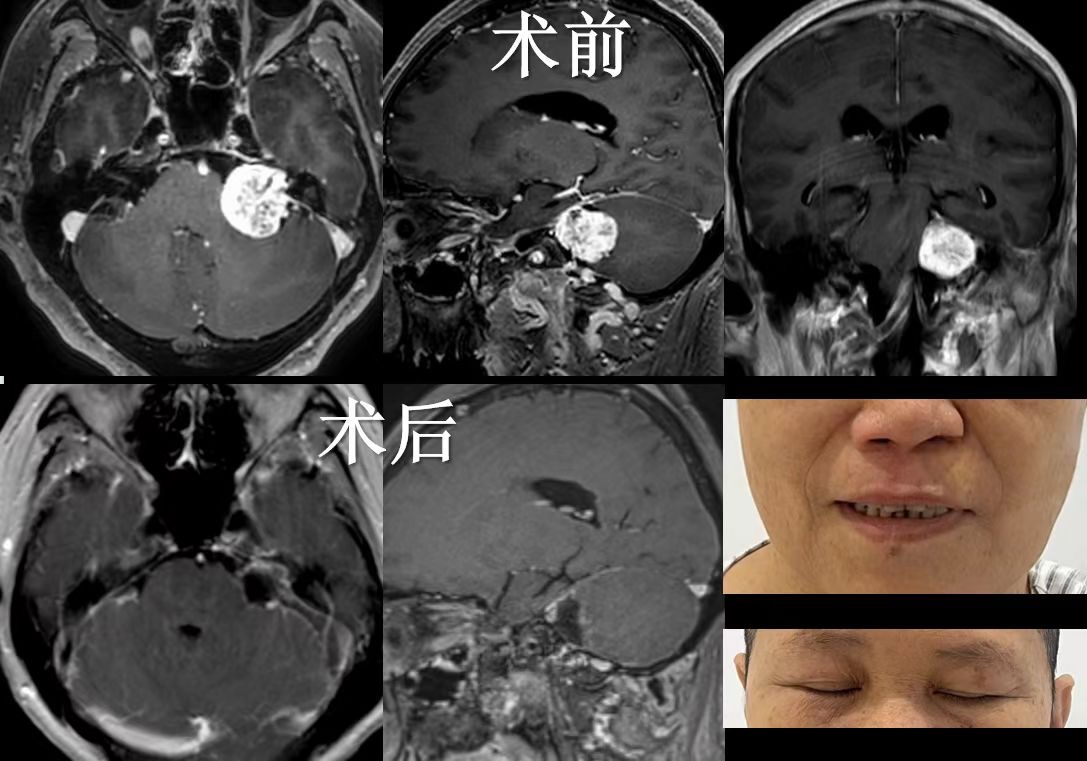

MRI(磁共振成像): 是首选侦探,能清晰“拍”出肿瘤的位置、大小以及与周围神经、血管、脑干的亲密关系,如同绘制一份精准的“敌情地图”。

“精准拆除”(显微外科手术): 这是治疗的主要手段。目标是在保护面神经功能(避免面瘫)和尽可能保留残余听力的前提下,安全、彻底地移除肿瘤。手术如同在头发丝般纤细的神经丛林中拆弹,需要极高精度的“雕刻”技术。